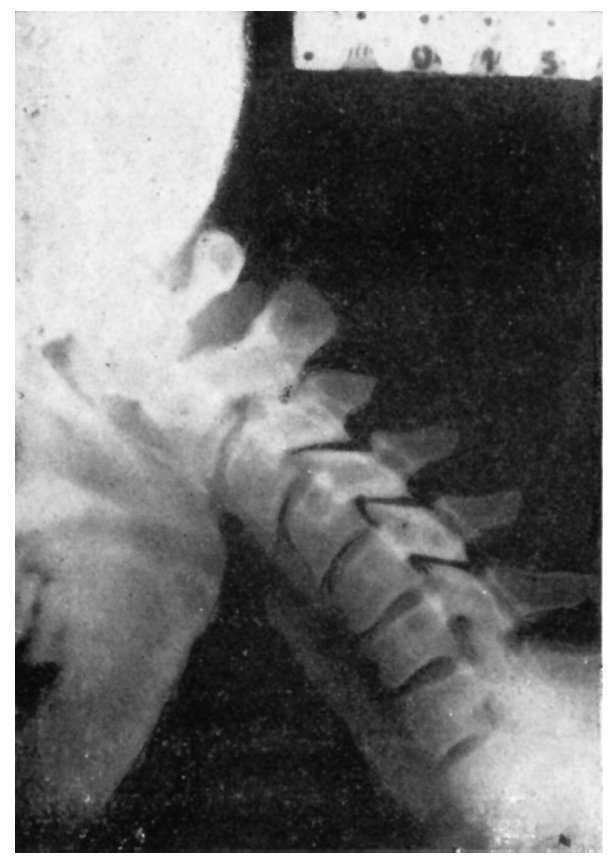

Figura 6 A.Caso núm. 1. E. A. G. Discosis 5-6a C.

Figura 6 B.Caso núm. 1. E. A. G. Radiografía en extensión. Anquilosis perfecta.

Figura 6 C.Caso núm. 1. E. A. G. Radiografía en flexión. Anquilosis perfecta.